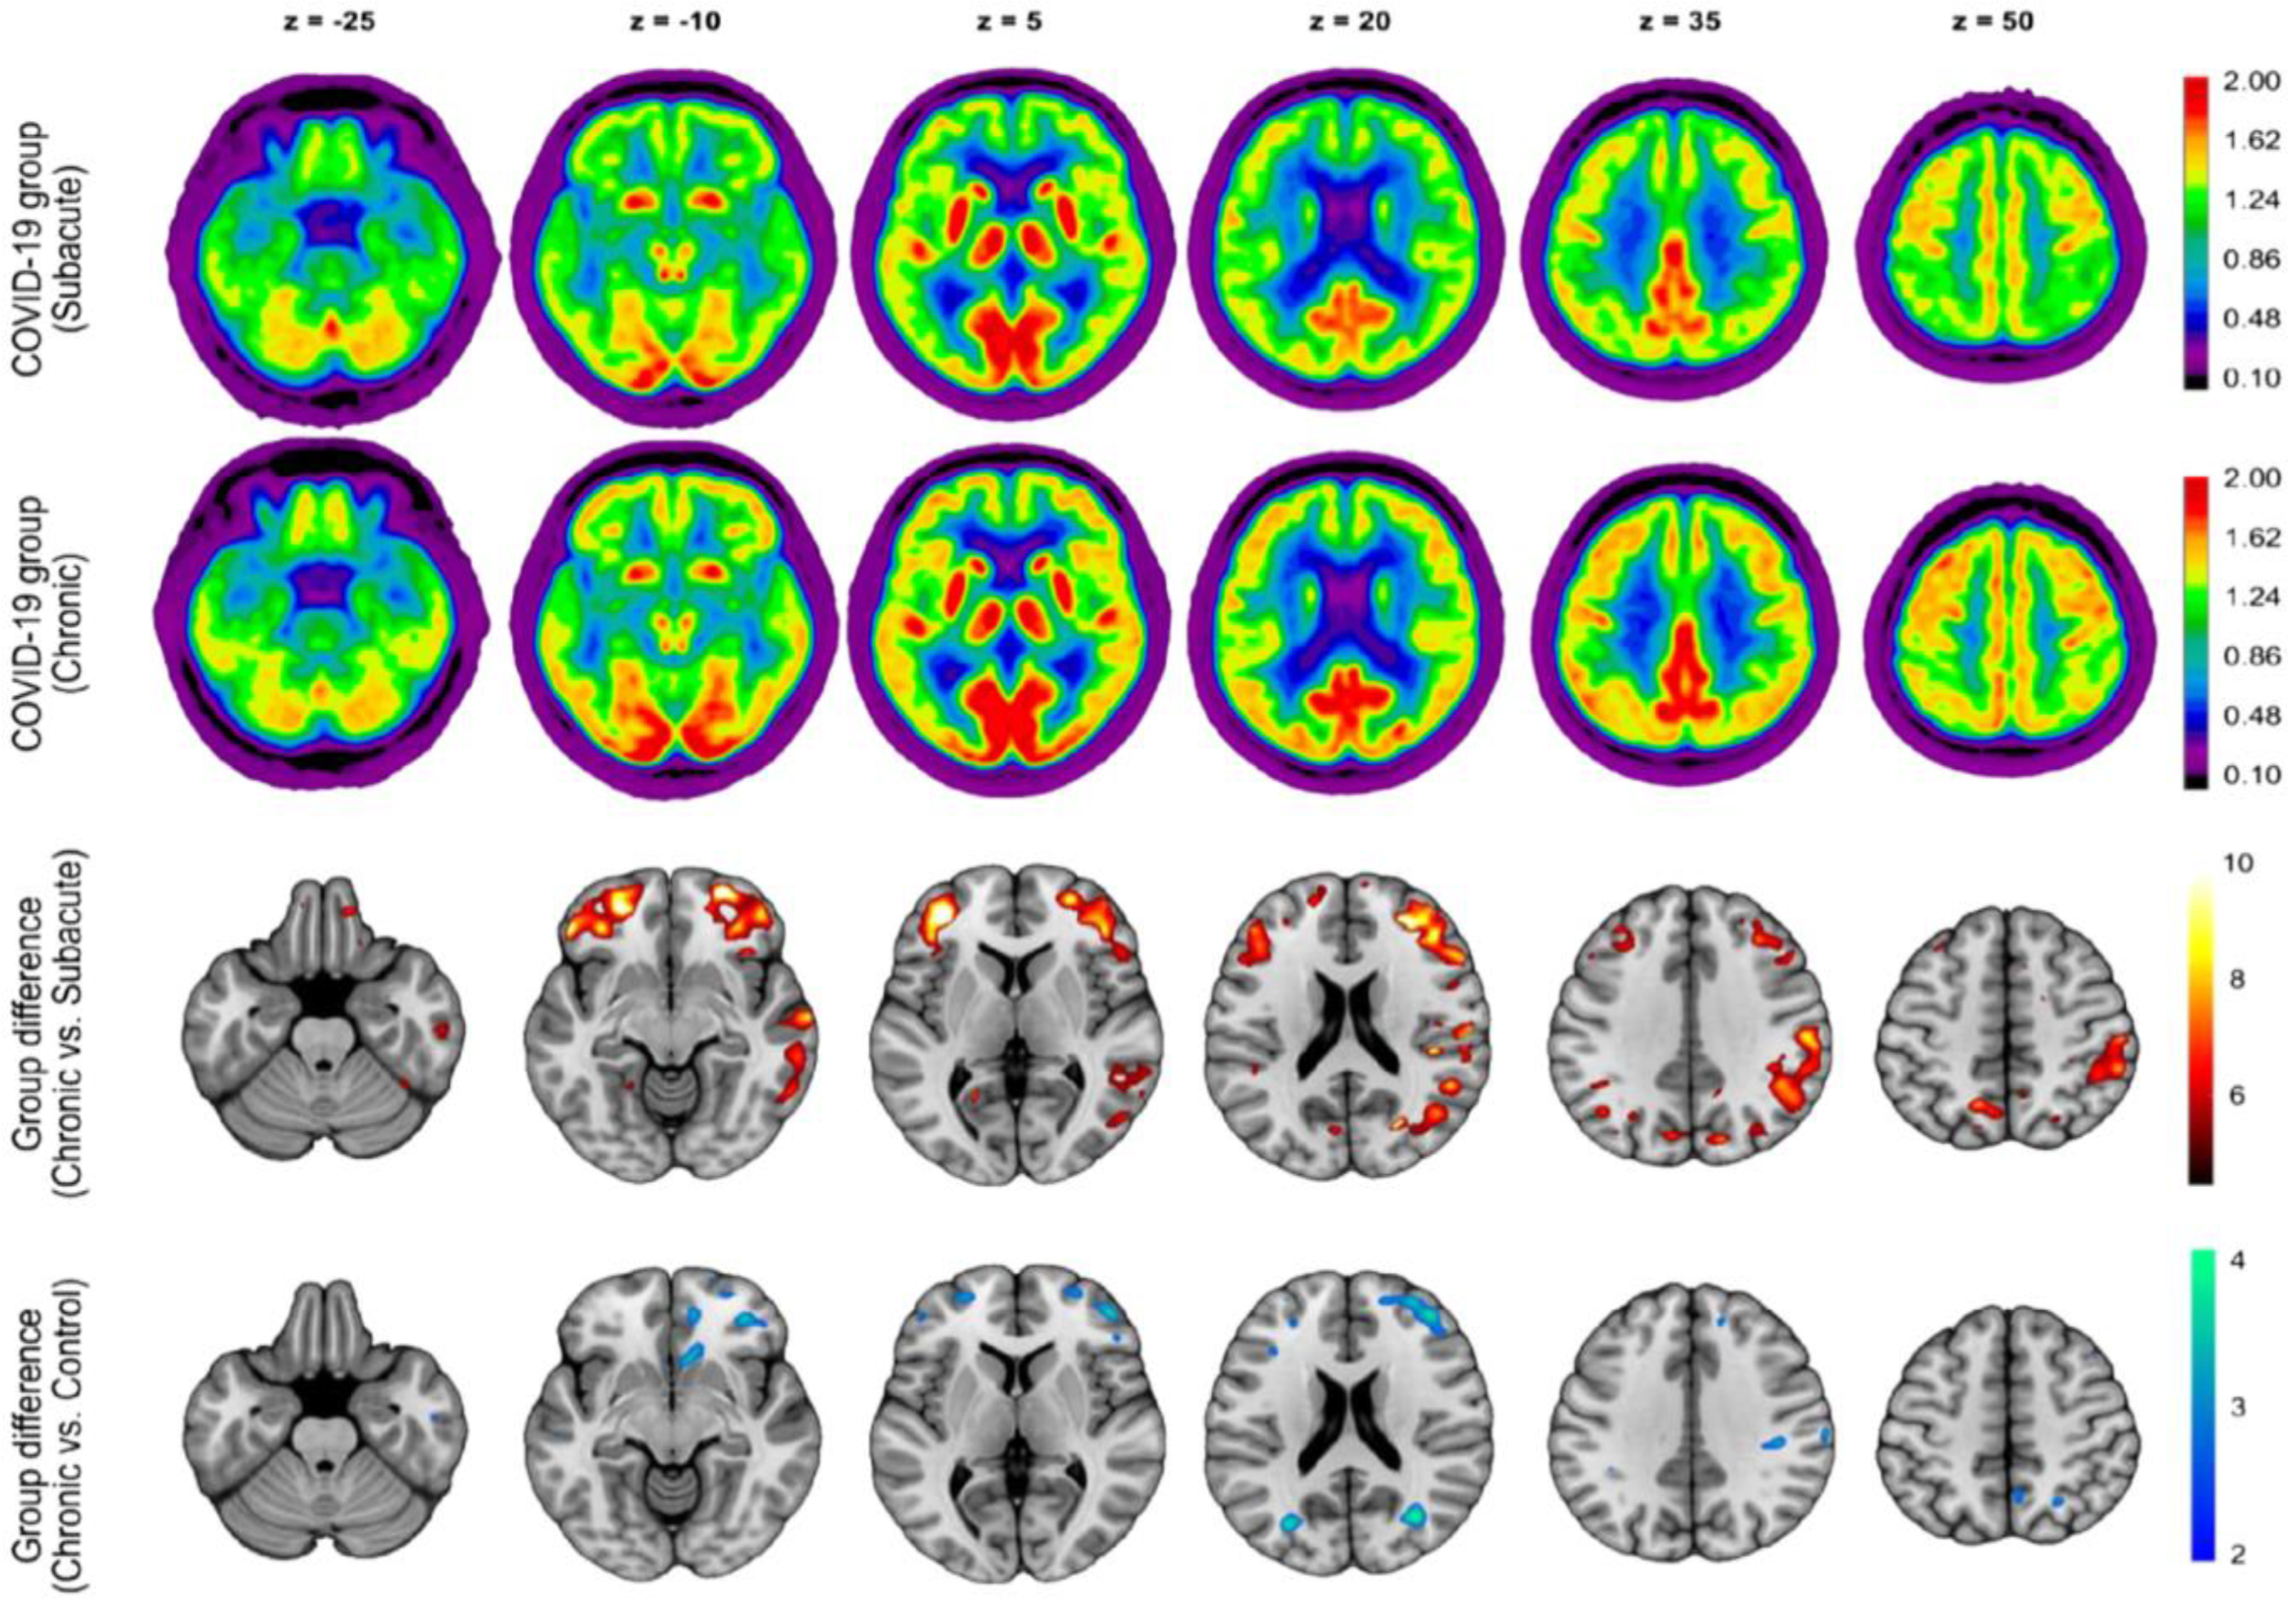

| Blazhenets et al. [55] | Frontoparietal and temporal regions | Mild cognitive impairment (assessed using MoCA) | 6 months (approximately) | Prospective cohort/8 subjects (6 males and 2 females) |

- Blazhenets, G.; Schröter, N.; Bormann, T.; Thurow, J.; Wagner, D.; Frings, L.; Weiller, C.; Meyer, P.T.; Dressing, A.; Hosp, J.A. Slow but Evident Recovery from Neocortical Dysfunction and Cognitive Impairment in a Series of Chronic COVID-19 Patients. J. Nucl. Med. 2021, 62, 910–915. [Google Scholar] [CrossRef] [PubMed]

- Dressing, A.; Bormann, T.; Blazhenets, G.; Schroeter, N.; Walter, L.I.; Thurow, J.; August, D.; Hilger, H.; Stete, K.; Gerstacker, K.; et al. Neuropsychologic Profiles and Cerebral Glucose Metabolism in Neurocognitive Long COVID Syndrome. J. Nucl. Med. 2022, 63, 1058–1063. [Google Scholar] [CrossRef]